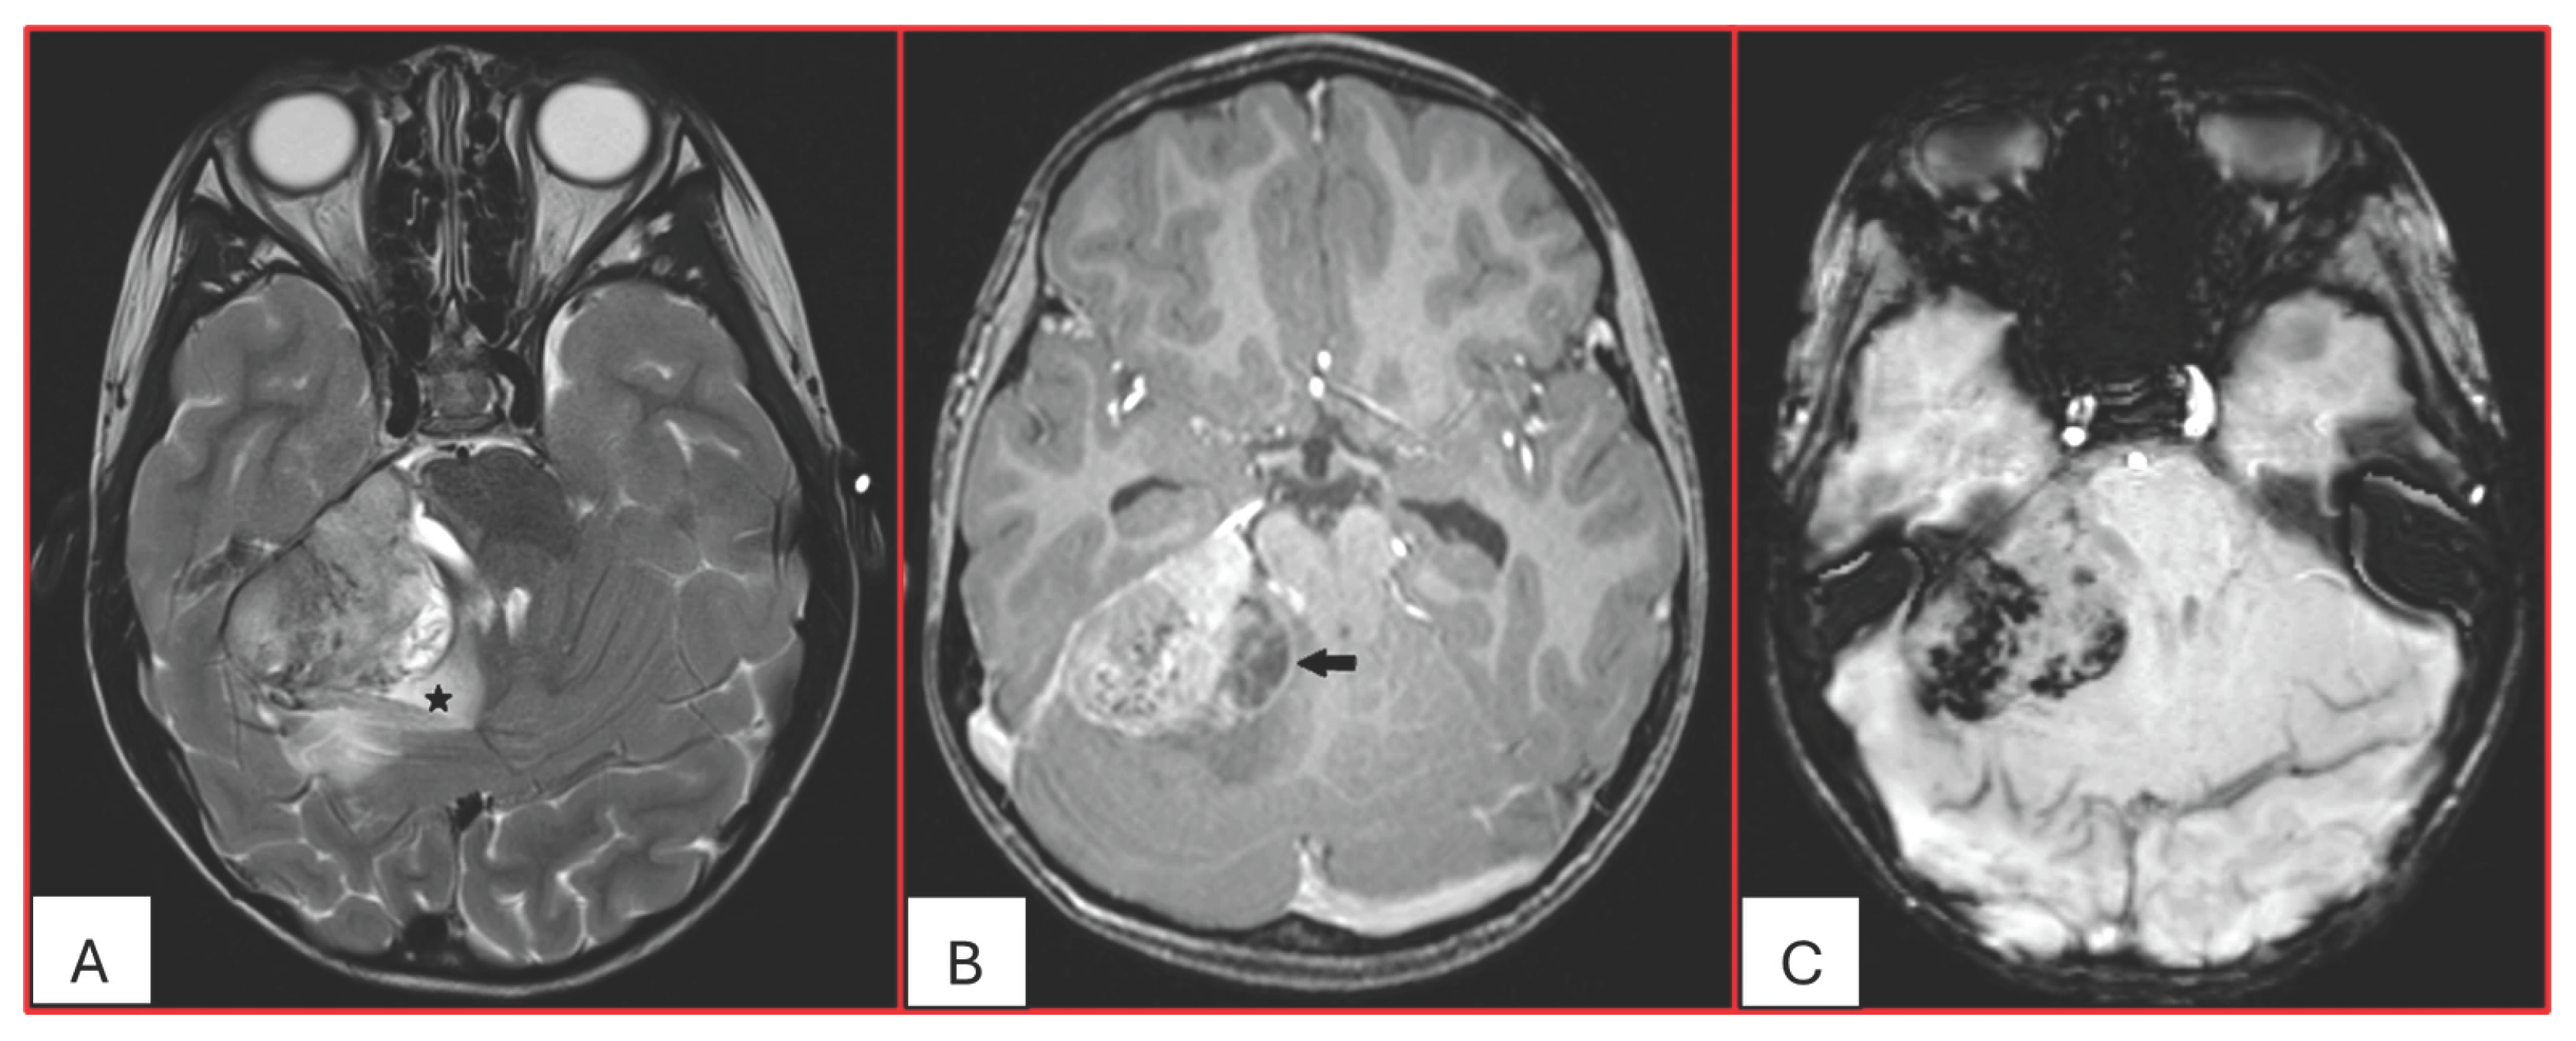

On computed tomography (CT), AT/RTs typically appear hyperdense owing to their high cellularity, and calcifications are frequently identified. Magnetic resonance imaging (MRI) findings are variable on both T1- and T2-weighted sequences; however, restricted diffusion is usually present. Cystic or necrotic components, as well as intratumoral hemorrhage, are common features [15]. Arslanoglu et al. described the presence of eccentrically positioned cysts with peripheral wall enhancement as a potentially distinguishing characteristic of infratentorial AT/RTs (Figure 1). The pattern and degree of contrast enhancement are variable, further reflecting the histopathologic heterogeneity of these neoplasms (Figure 2 and Figure 3). A characteristic pattern of band-like enhancement surrounding a central cystic or necrotic area was observed in 38% of MRIs from a series of 32 patients [16].

Figure 1. Five-year-old male with ATRT-MYC subgroup. (A). Axial T2-weighted image demonstrates a large extra-axial mass in the posterior fossa centered at the right cerebellopontine angle of intermediate heterogeneous signal. There is surrounding vasogenic edema (star) and mass effect. (B). Axial post contrast T1-weighted image shows heterogeneous enhancement with eccentric peripherally enhancing cystic component (arrow). (C). Axial SWI demonstrates multiple internal foci of susceptibility reflecting hemorrhagic content (no calcifications on the concurrent CT). This tumor was associated with leptomeningeal spread at the time of diagnosis into the internal auditory canals and along the cerebellar folia.